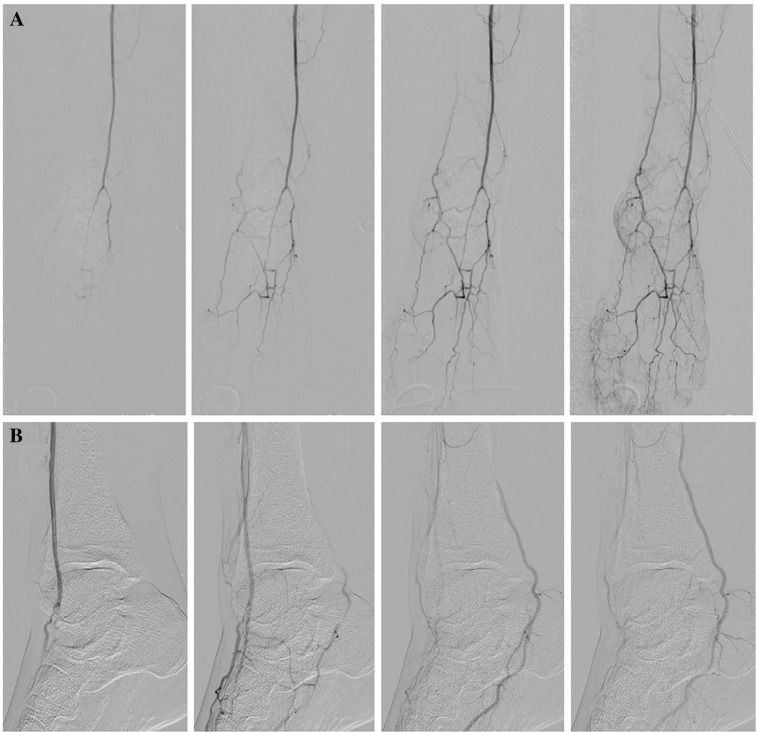

Aneurysms of the tibioperoneal trunk (TPT) with peripheral arterial lesions are extremely rare. We present a case of a 68-year-old man who underwent surgical treatment for a mycotic aneurysm of the TPT. This report highlights the importance of en bloc surgical resection of the mycotic aneurysm and an appropriate approach with an air tourniquet for the prevention of injuries to the adherent tissues.